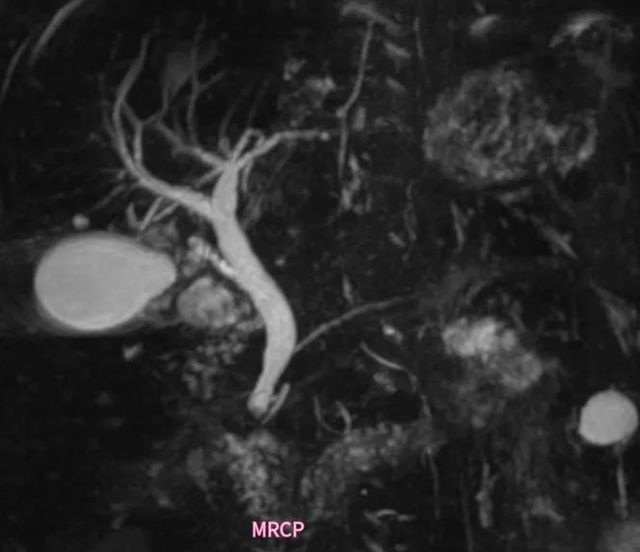

MR胰胆管造影(MR cholangio-pancreatography,MRCP)用于观察胰胆管系统解剖和病理形态的技术(图1MRCP)(图2MRCP),它可以展示胰胆管形态和组织结构为自然状态的表现,用于恶性肿瘤、结石、胆管先天性病变、狭窄和急慢性胰腺炎等诊断。